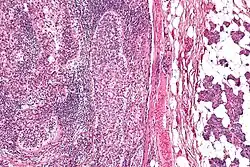

Das Talgdrüsenkarzinom ist ein seltener, aber aggressiver Tumor im Kopf-Halsbereich, der von den Talgdrüsen ausgeht. Man unterscheidet das okuläre Talgdrüsenkarzinom, das die Augenlider betrifft, vom extraokulären Talgdrüsenkarzinom, das den übrigen Körper befällt.[1]

Dieser Tumor tritt vor allem bei über 70-Jährigen auf und befällt meist das Auge. Der knotige, rötliche oder gelbe Tumor wächst schnell, ist leicht mit Entzündungen zu verwechseln und hat eine Größe von fünf Millimeter bis fünf Zentimeter.